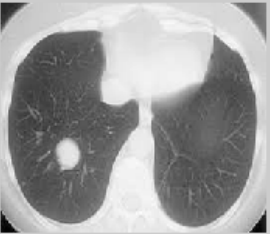

The ELCAP [23] and LIDC benchmark datasets [24, 25] are used to assess how well the suggested method performs in lung nodule identification. The DIOCOM format is used to store lung CT images, and each scan has 512 pixels in width and 512 pixels in height. Figure 5 displays the image of a human lung with a tumor that is used as the input image. The input image is clustered using the FCM technique and then the clustered output is segmented into the tumor region using the histogram approach. The FCM algorithm takes less time to execute than the FLICM and KWFLICM algorithms, but it is unable to cluster images with outliers or noise like salt and pepper. The FCM clustering and segmentation image is displayed in Figure 6. Given an input image, the FLICM algorithm is utilized to do the clustering. The tumor zone is divided from the FLICM algorithm's clustered output using the histogram approach. While the FLICM approach takes longer to execute than the other two, it produces better clustering results when compared to FCM in cases where the image contains outliers or salt and pepper noise. Figure 7 shows the FLICM segmentation and clustering image.

Figure 5. Input image

(a)

(b)

Figure 6. (a) FCM clustering image; (b) segmented image